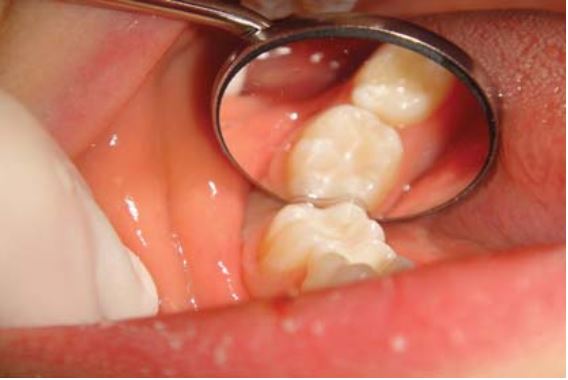

Trám răng ở trẻ thường được thực hiện trong vòng 5 phút hoặc ít hơn 5 phút và thường không cần gây tê hoặc đặt đê. Loại bỏ phần ngà sâu bằng mũi khoan tròn lớn với tay khoan chậm.

Có thể sử dụng cây nạo ngà, nhưng phải rất cẩn thận vì dễ có nguy cơ thủng vào buồng tủy khi lấy đi một lượng ngà lớn (H1.6).

Có thể sử dụng một tấm chặn (dri – angle) để banh má khi trám các răng sau. Khi trám những răng cối sữa hàm dưới thì sử dụng thêm tấm chặn thứ 2 để banh lưỡi (H1.7).